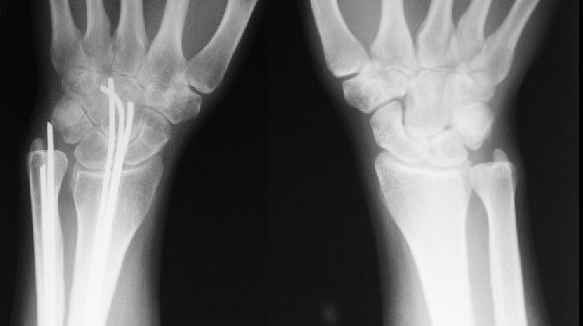

Re: Несращение предплечья

> Укорочение во многом связано с угловой деформацией, после устранения которой, увеличится и длина луча. Сделайте для сравнения прямую рентгенограмму л/з сустава на здоровой стороне

Помимо отсутствия физиологической кривизны лучевой кости, есть еще и рекурвация, поэтому, после устранения углов длина вряд ли увеличится.

Сравнительные снимки в приложении

> Исправить ось луча, остеосинтез пластиной LCP с костной аутопластикой губчатой крошкой. После этого решить на операции: нужно ли укорачивать локтевую? Если "да", то после резекции фиксировать пластиной.

Тоже склоняемся к данному варианту. Адаптивная резекция лучевой кости позволит обойтись без костной пластики.